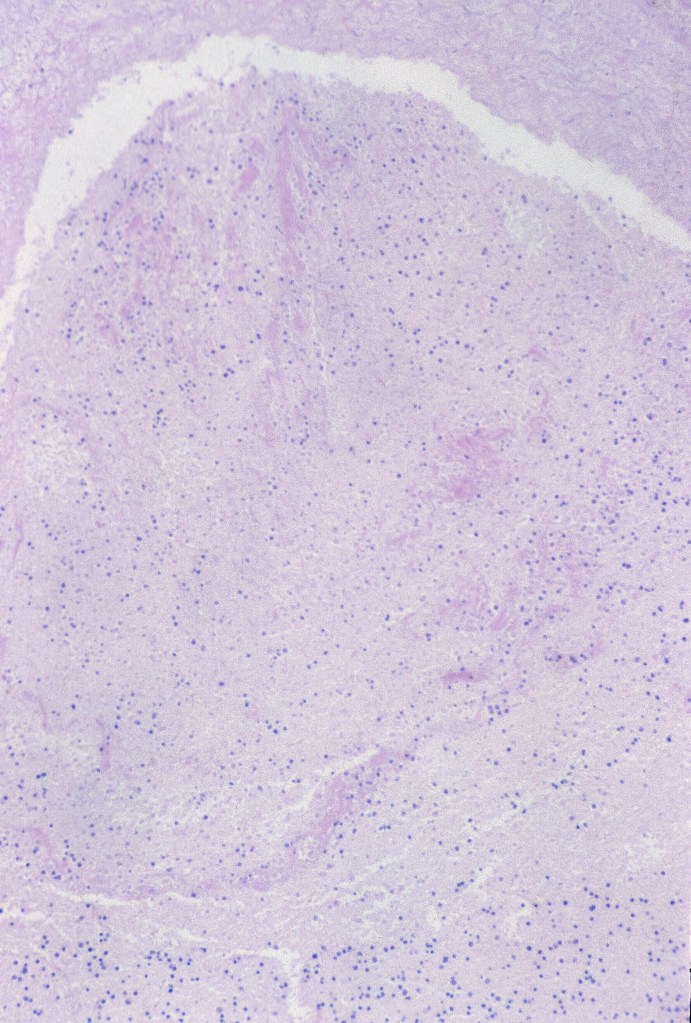

Hematopoiesis: The liver is a major site of fetal hematopoiesis. Erythropoiesis and megakaryocytopoiesis occur in the liver sinusoids. Erythropoiesis is increased with conditions requiring increased production such as fetal hemolysis or hemorrhage, and in macrosomic infants of diabetic mothers2. The extent of erythropoiesis decreases with gestational age (Fig 4a, b).